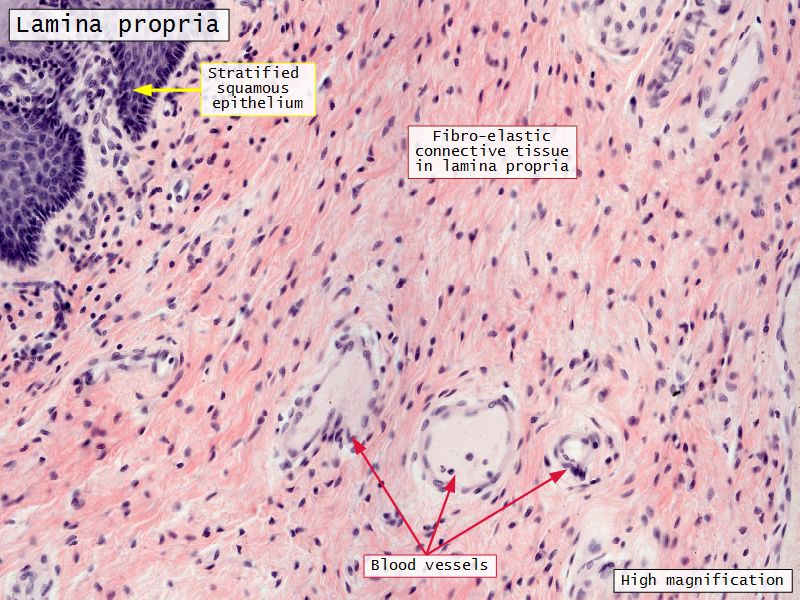

Mucosa

- Epithelium

- Lamina propria

Lamina propria

- Loose connective tissue

- Reticular fibres

- Fibroblasts

- Mast cells

- Lymphoid cells

Mucosa

- Epithelium

- Thick stratified squamous nonkeratinized

- Lamina propria

- Fibroelastic connective tissue

- Rich in elastic fibres

- Contains lymphoid elements

- Deep portion highly vascular

- No glands